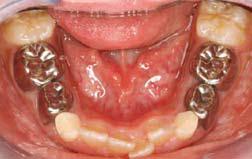

活動假牙分為全口假牙托和部分假牙托。前者幫助全口無牙的病人,原理是利用口腔的肌肉把假牙托固定在頜骨上;後者幫助失去部分牙齒的病人,配戴方法是把假牙托底部伸延出來的金屬扣環固定在其他牙齒上。若病人頜骨已植上鈦植體,全口及部分假牙托便可利用螺絲釘的接合裝置固定在鈦植體上。

■全口假牙托